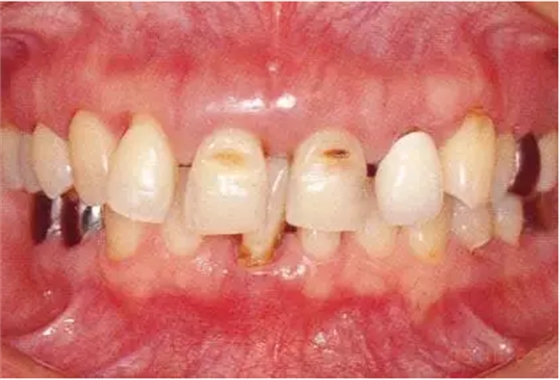

病例9

對患有重度牙周疾病的患者,采取包括了正畸、牙周、種植、修復(fù)在內(nèi)的綜合性治療的病例

2222222222.png

▲圖19-1

40歲,女性。來院主訴為牙齦出血,牙體晃動?;颊卟晃鼰?,因此沒有全身性問題。有明顯的牙周炎,發(fā)生了牙體移動,前牙區(qū)前突。下頜右側(cè)磨牙缺失,醫(yī)生認(rèn)為有必要進(jìn)行包括牙周修復(fù)、正畸治療、種植治療等在內(nèi)的綜合性治療。